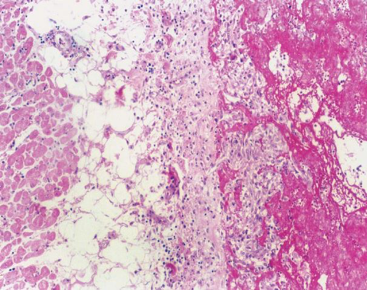

肝:体积增大,边缘钝圆,包膜紧张,切面见红黄相间的花纹,镜下见肝小叶中央静脉及附近肝血窦扩张,充满红细胞,肝细胞索变窄,肝小叶周边部分肝细胞脂肪变性。

(图3-3)